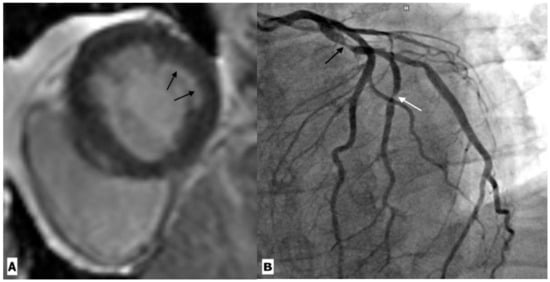

2.4. Coronary Artery Diseases

| Coronary artery disease | Raggi, P. et al. | Prospective observational study | 843 patients | CT | In a median follow-up of 2.8 years, it was seen that a CAC score of 100 was associated with 3.3-times higher odds of myocardial infarction, independent of gender and age. |

| Zanni, M.V. et al. | Cross sectional study | 101 patients and 41 controls | CTA | The study showed an increased prevalence of low-attenuation coronary plaque in HIV-positive men compared to age-matched HIV-negative healthy controls. | |

| Hoffmann, U. et al. | Cohort study | 755 HIV infected patients | CTA | Atherosclerotic plaque was seen in 49% patients. Luminal obstruction of at least 50% was rare (3%), but vulnerable plaque were more frequently observed (23%). Overall, 35% of patients demonstrated coronary artery calcium score scores greater than 0. IL-6. LpPLA2, oxLDL, and MCP-1 levels were higher in those with plaque compared to those without. | |